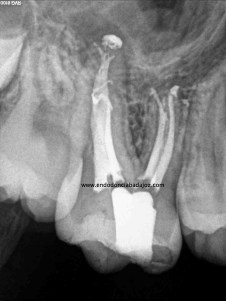

Esta última foto corresponde con un caso de un primer molar superior que la Rx no me esperaba que tuvieses tres conductos mesiales:

Son casos complicados, este en particular, por la ligera curva apical, que se agrava con la curva coronal, con lo que debemos aliviar modificando la apertura y acceso del tercio coronal con ultrasonidos e instrumentación.

Usamos los sistemas Pathfiles y las Mtwo, consiguiendo una buena preparación de los conductos

El sistema de obturación que usamos fue condensación vertical por ola de continua: